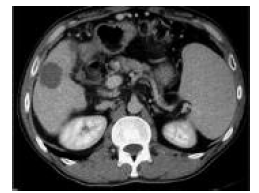

One such combined strategy is the combination of radiofrequency ablation and transarterial chemoembolization. A combination of transarterial chemoembolization followed by radiofrequency ablation has been used to minimize heat loss because of perfusion-mediated tissue cooling and to increase the therapeutic effect of radiofrequency ablation (Figures 5-9).26 Radiofrequency ablation and transarterial chemoembolization are more effective for complete tumor necrosis rate in patients with hepatocellular carcinoma.21,27 Local tumor progression rate was significantly lower in the transarterial chemoembolization and radiofrequency ablation-treated group than in the radiofrequency only ablation group (6%-39%).28

Figure 7 and 8. Ultrasonography Visualization of Hepatocellular Carcinoma Nodule Before and After Selective Chemoembolization

Figure 9. One-month Follow-Up, Computed Tomography Images of the Hepatocellular Carcinoma Nodule That Combined (Drug Eluting BeadTransarterial Chemoembolization + Radiofrequency Ablation) Procedure Was Applied. No Residual or Recurrent Lesion